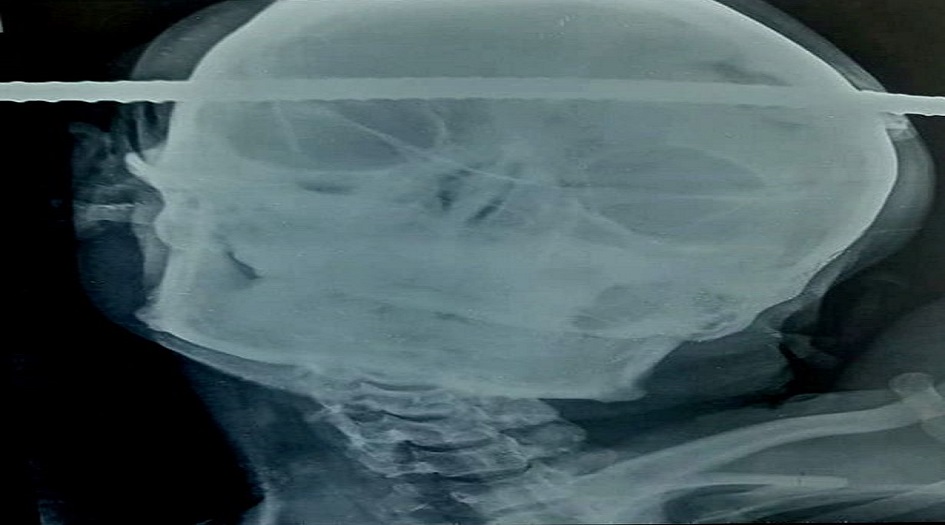

وسقط سانجاي باهي، البالغ من العمر 21 عاما، أثناء بنائه بئرا ملكا له، ما عرضه لإصابة في كل من يده وجمجمته، حيث اخترق قضيب حديدي رأسه مباشرة في هذه الحادثة، ليمر من الجانب الأيمن إلى الجانب الأيسر.

ونقل باهي إلى المستشفى بسرعة لإجراء عملية جراحية طارئة، وظل في كامل وعيه طوال هذه الأحداث بأكملها، بما في ذلك العملية التي أجريت على دماغه والتي استمرت 90 دقيقة لإزالة القضيب الصدئ من جمجمته، والذي اخترق الفص الصدغي الأيمن في المنطقة الأمامية اليسرى.